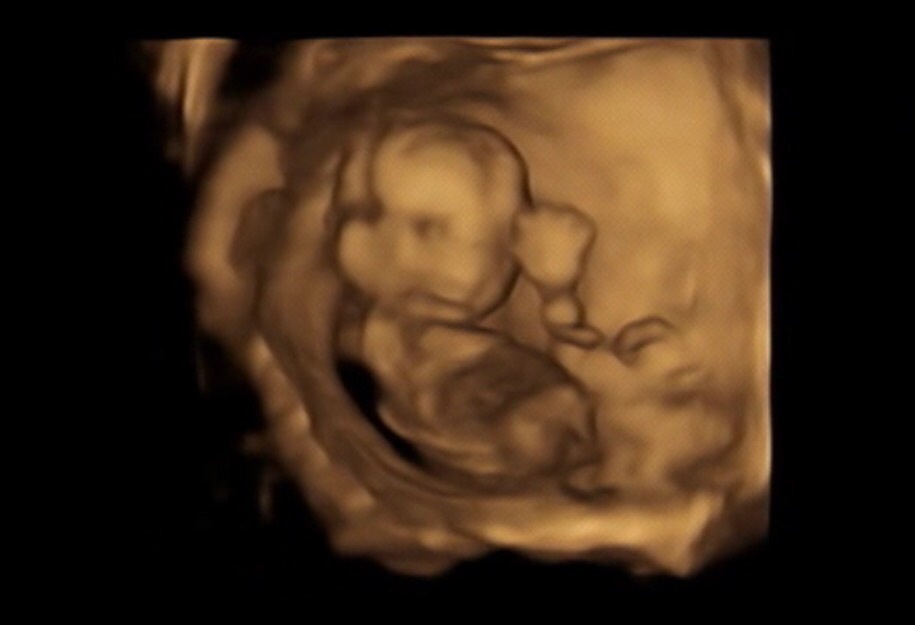

こーんなに ちっこかった

赤ちゃん 。